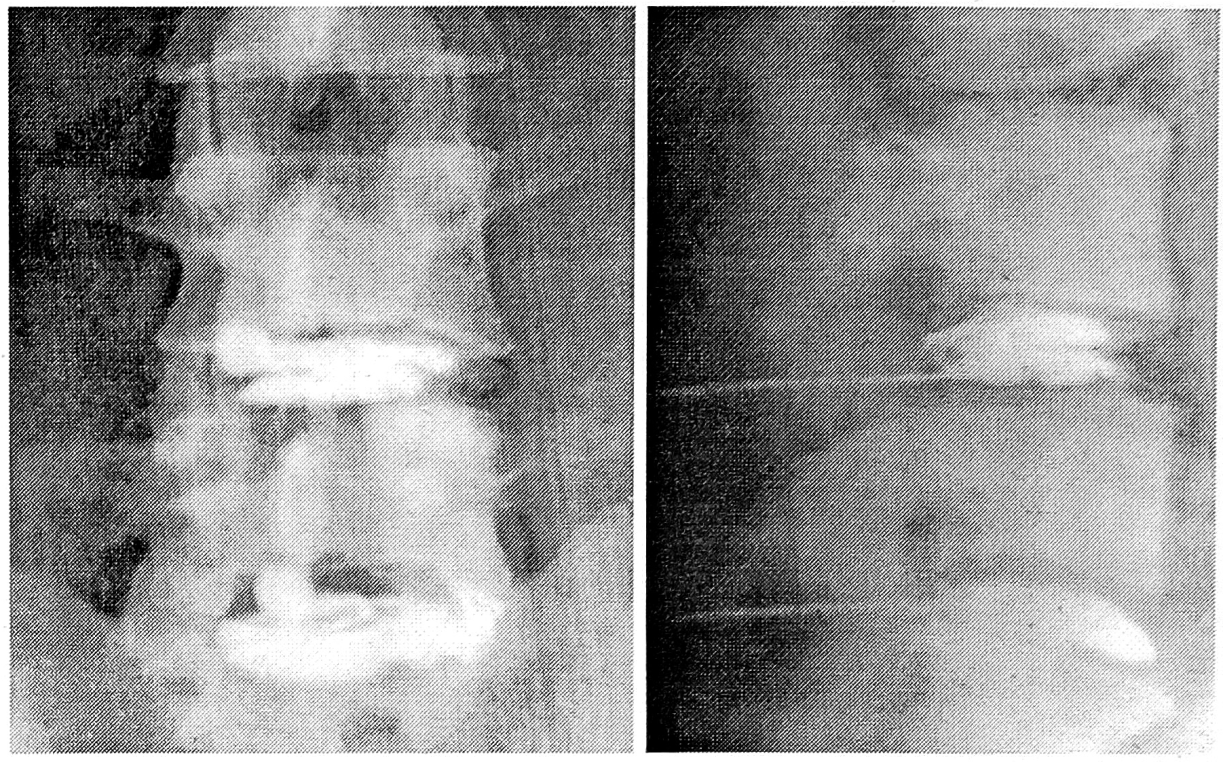

Дискографическая картина при подсвязочных и чрессвязочных разрывах межпозвонковых дисков была различной. Тень контрастного вещества при подсвязочных грыжах располагалась как в самом диске, так и вне его, принимая самые разнообразные формы в зависимости от патоморфологических изменений. Наиболее часто наблюдались конусовидная тень, а также тень в форме песочных часов (см. рис. 4).

Рис. 4. Подсвязочные- грыжи L4—5, L5—S1 дисков.

Емкость диска превышала 1,5 мл, достигая в отдельных случаях 2 мл (большего количества контрастного вещества мы не вводили). Введение контрастного вещества сопровождалось появлением боли в нижней конечности.

На дискограммах внутриспонгиозного типа отмечалось заполнение контрастным веществом грыж Шморля, т.е. дефектов спонгиозной ткани тела позвонка (см. рис. 10).

Рис. 10. Внутриспонгиозный тип дискограмм (грыжи Шморля L2, L4 позвонков).

В 17 случаях контрастное вещество не выходило за пределы склеротической каймы вокруг грыж Шморля. Остальные 5 случаев демонстрировали дальнейшее продвижение контрастного вещества в глубь тела позвонка на 2—5 мм. Мы располагаем также двумя наблюдениями внутриспонгиозного пролабирования студенистого ядра без признаков грыжи Шморля на стандартных спондилограммах (см. рис. 5 и 11). Емкость диска составляла 1,0—1,8 мл. Введение контрастного вещества не сопровождалось болью. Высота межтеловых промежутков была умеренно снижена.